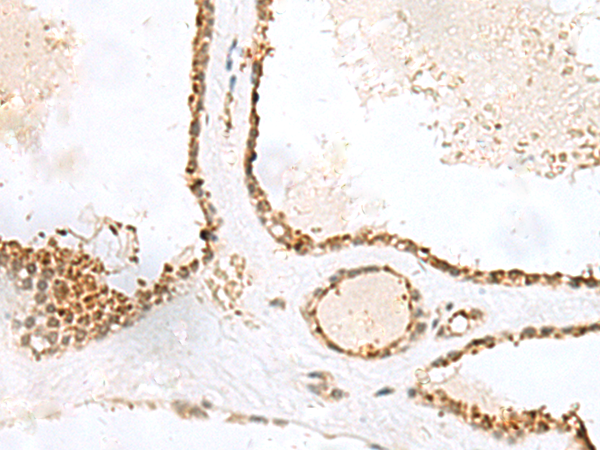

分类: 科研抗体货号: P09905别名: EIF-2B; EIF2Bgamma应用: IHC反应种属: Human, Rat